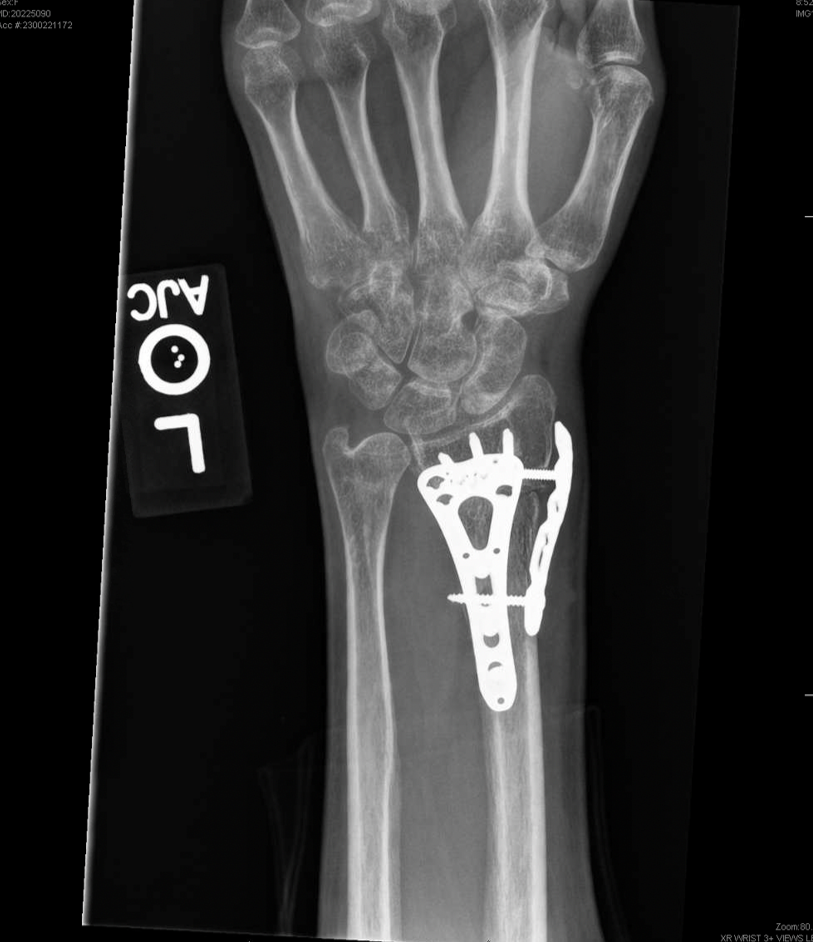

A modified volar Henry approach to the distal radius was utilized in which the incision was made between the radial artery and the flexor carpi radialis tendon. The high-energy nature of the multilevel injury to the left upper extremity resulted in a highly unstable distal radius fracture pattern with a significant amount of metaphyseal radial column comminution. The decision was made to proceed with fragment-specific fixation, and a radial column plate was placed underneath the first extensor compartment in addition to a volar locking plate (Fig. 3).

Figure 3: Post-operative left wrist X-ray. Status post internal fixation with a radial column plate and volar locking plate.